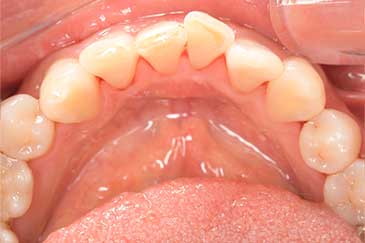

CASE 9

Before

After

基本情報

| 年齢・性別 | 49歳・男性 |

|---|---|

| 主訴 | 定期検診 |

| 治療内容 | スケーリング |

| 治療期間 | 1回30分、2日間 |

| 治療費 | 約1,500円(保険診療) |

| リスク・副作用 | 知覚過敏、出血 |

| 治療方針 | 歯肉縁上歯石を除去してから、14枚法を撮影して歯肉縁下歯石を除去します。歯周ポケットが深く、歯石が残っている部位はフラップ手術を行います。 今後一年程かけて虫歯の治療と並行して歯周病治療、生活習慣の改善を行いプラークコントロールができるように指導します。 |

| 担当者所見 | 久しぶりの歯科医院受診のため、2日に分けて歯石を除去しました。 |